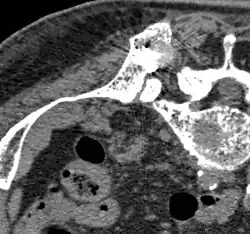

- Comparaison scanner/IRM pour des métastases ostéolytique d'un cancer du sein dans la colonne vertébrale

Scanner sagittal reconstruit, représentation dans la fenêtre osseuse. Comme la patiente avait des métastases dans toutes les régions du corps, elle ne pouvait pas lever les bras pour l'examen, ce pourquoi les mains sont présentées.

Scanner sagittale, parties molles. Outre les métastases dans la colonne vertébrale, qui envahissent en partie le canal médullaire vers l'arrière, métastases aussi dans le sternum. Plus des métastases dans le foie.